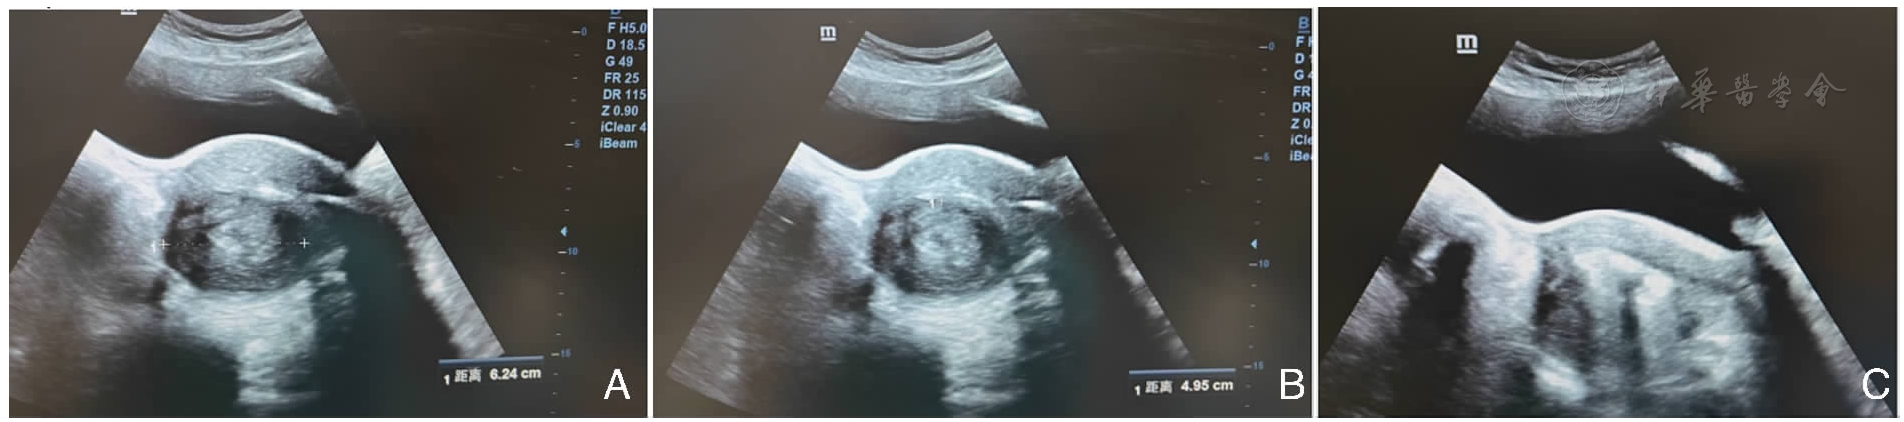

图1 3型子宫肌瘤的宫腔镜术中超声监测注:A.子宫后壁肌瘤 长6.24 cm; B.子宫后壁肌瘤 宽4.95 cm;C.宫腔镜术中肌瘤切除术后,显露瘤腔